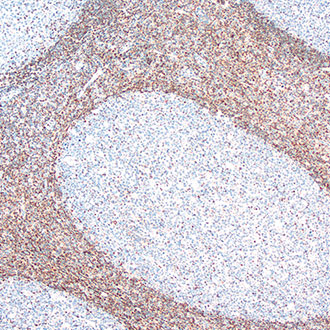

bcl-2

bcl-2 -